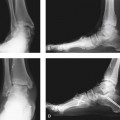

What are the indications for arthrodesis? At times a specific indication is obvious—for example, the presence of severe ankle arthritis will necessitate an arthrodesis for correction. A varus deformity associated with ankle arthritis and global foot cavus deformity is not ideally treated with a joint replacement (Figure 15-2). A triple arthrodesis is a good procedure, provided that the foot is correctly balanced with additional osteotomy and tendon transfer. The triple arthrodesis gained a poor reputation for correction of the cavus foot, particularly that associated with Charcot-Marie-Tooth disease, correctly named hereditary sensorimotor neuropathy. These arthrodesis procedures were performed in isolation, and as might be expected, the deformity recurred. The posterior tibial tendon inserts distal to the talonavicular joint, and unless the tendon is transferred, the medial foot deformity will gradually recur, with onset of adductovarus. Therefore, if a triple arthrodesis is thought to be the procedure of choice, it should be performed with appropriate transfer of the posterior tibial tendon, as well as additional tendon transfers as required (Figure 15-3).